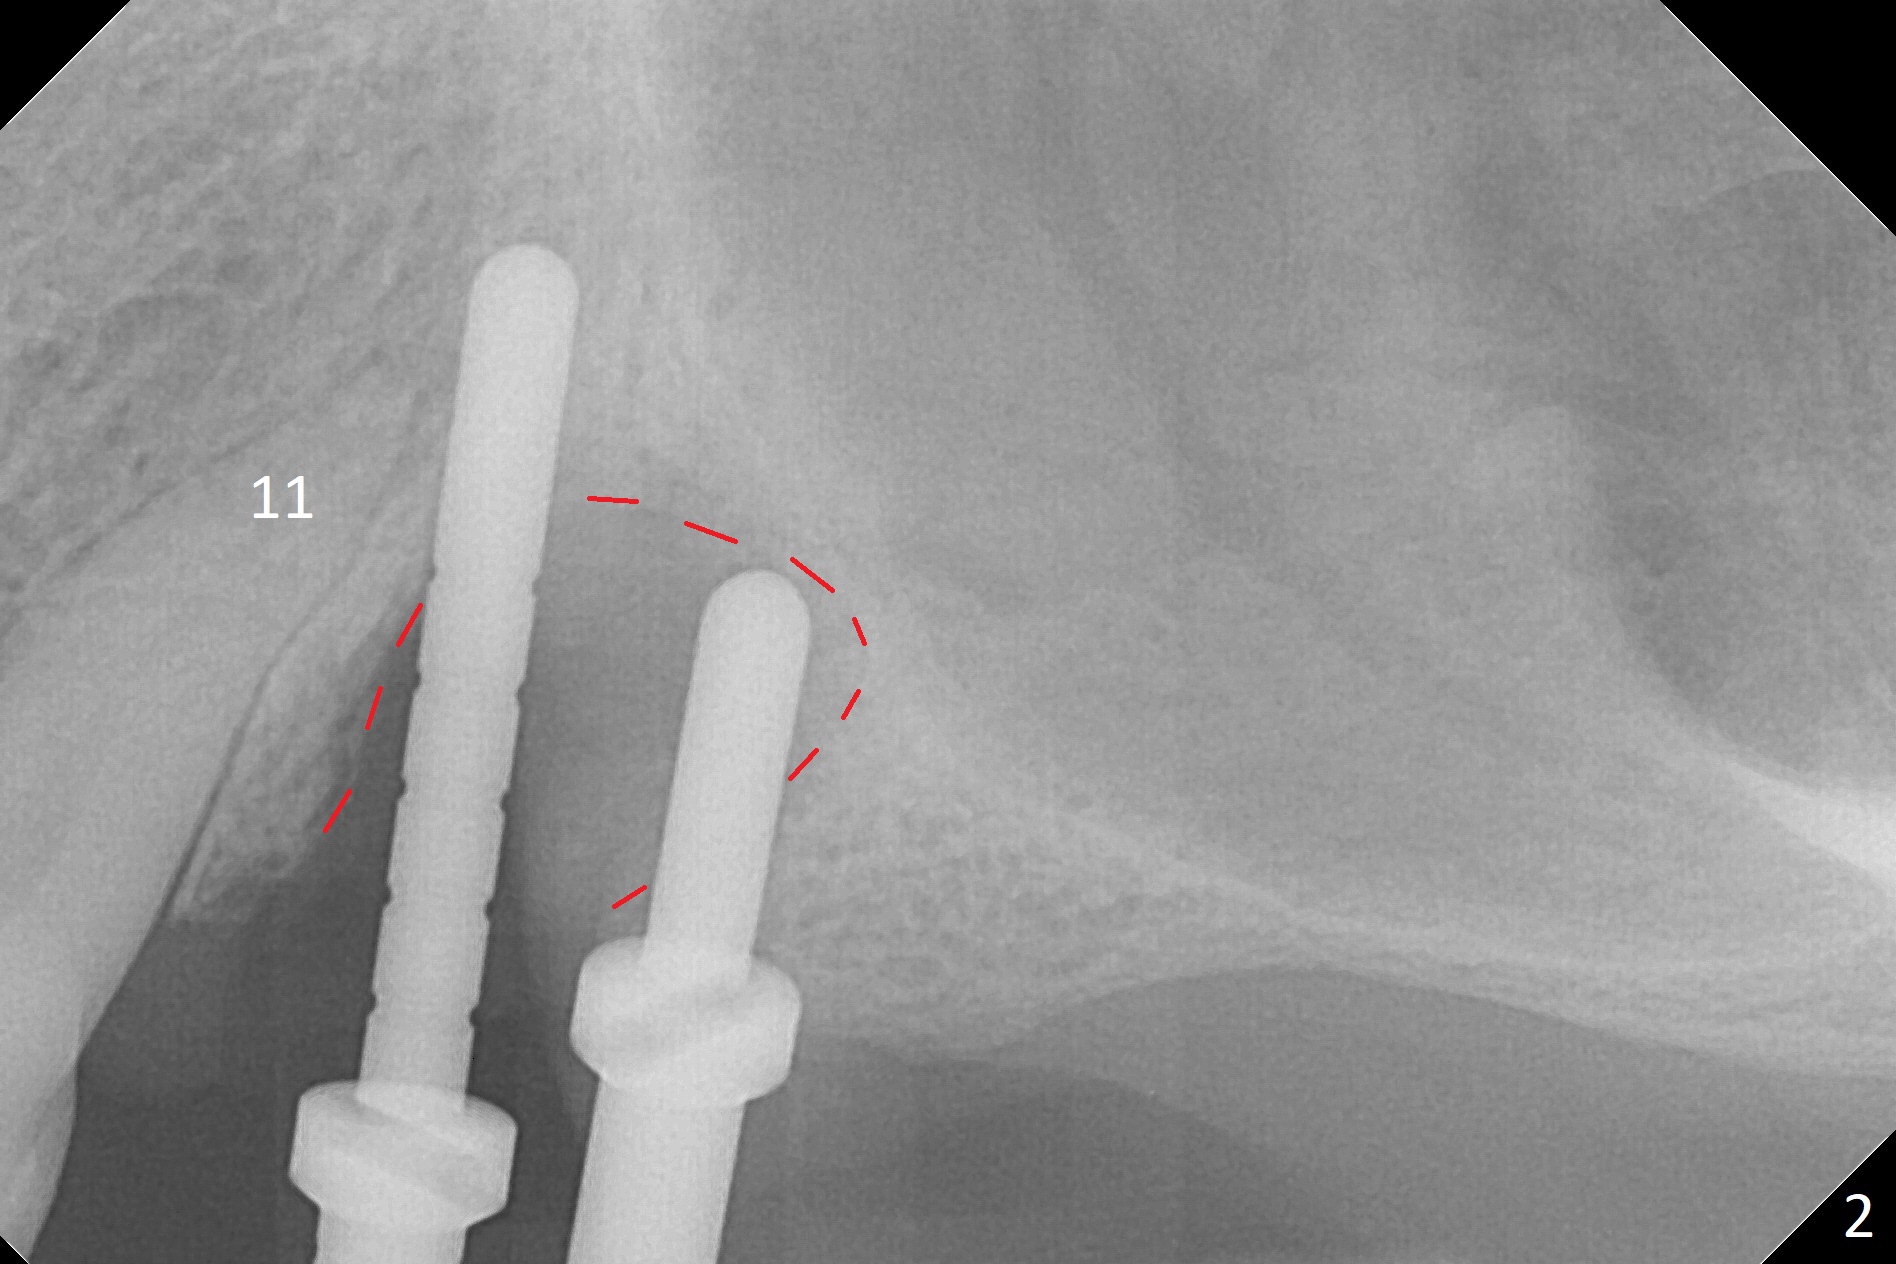

The buccal gingiva at #12 with vertical root fracture looks unhealthy (Fig.1). Osteotomy at #13 is initiated prior to #12 extraction. In fact the osteotomy happens in the extensive defect associated with #12 (Fig.2 red dashed line). To obtain primary stability, the osteotomy at #12 needs to be long, while that at #13 needs two-pointed fixation (Fig.3 *). After adjustment of trajectory at #12 and increase in diameter of the osteotomy at #13 (Fig.4), a 3.8x15 and 3.8x10 mm implants are placed (Fig.5). Following adjustment of implant depth (Fig.6), the implant at #12 becomes loose, while that at #13 tightens. With placement of abutments, an immediate splinted provisional is locked in place to stabilize the loose implant at #12 (Fig.7). The patient complains of cold sensitivity in the upper left quadrant, possibly related to the fact that the implant at #12 is close to the apex of the tooth #11. The position and trajectory of the initial osteotomies should be changed as shown in Fig.8 (white lines, as compared to Fig.2). There is no sensitivity 1 month postop. Impression is taken 4 months postop (Fig.9) after #13 mesiobuccal margin prep. The implants were placed too close to each other. The abutment screw at #13 is retightened 8 months post cementation. There appears no bone loss 9 months post cementation (Fig.10), while the tooth #11 has periapical infection with DL caries 1 year 7 months post cementation (Fig.11).